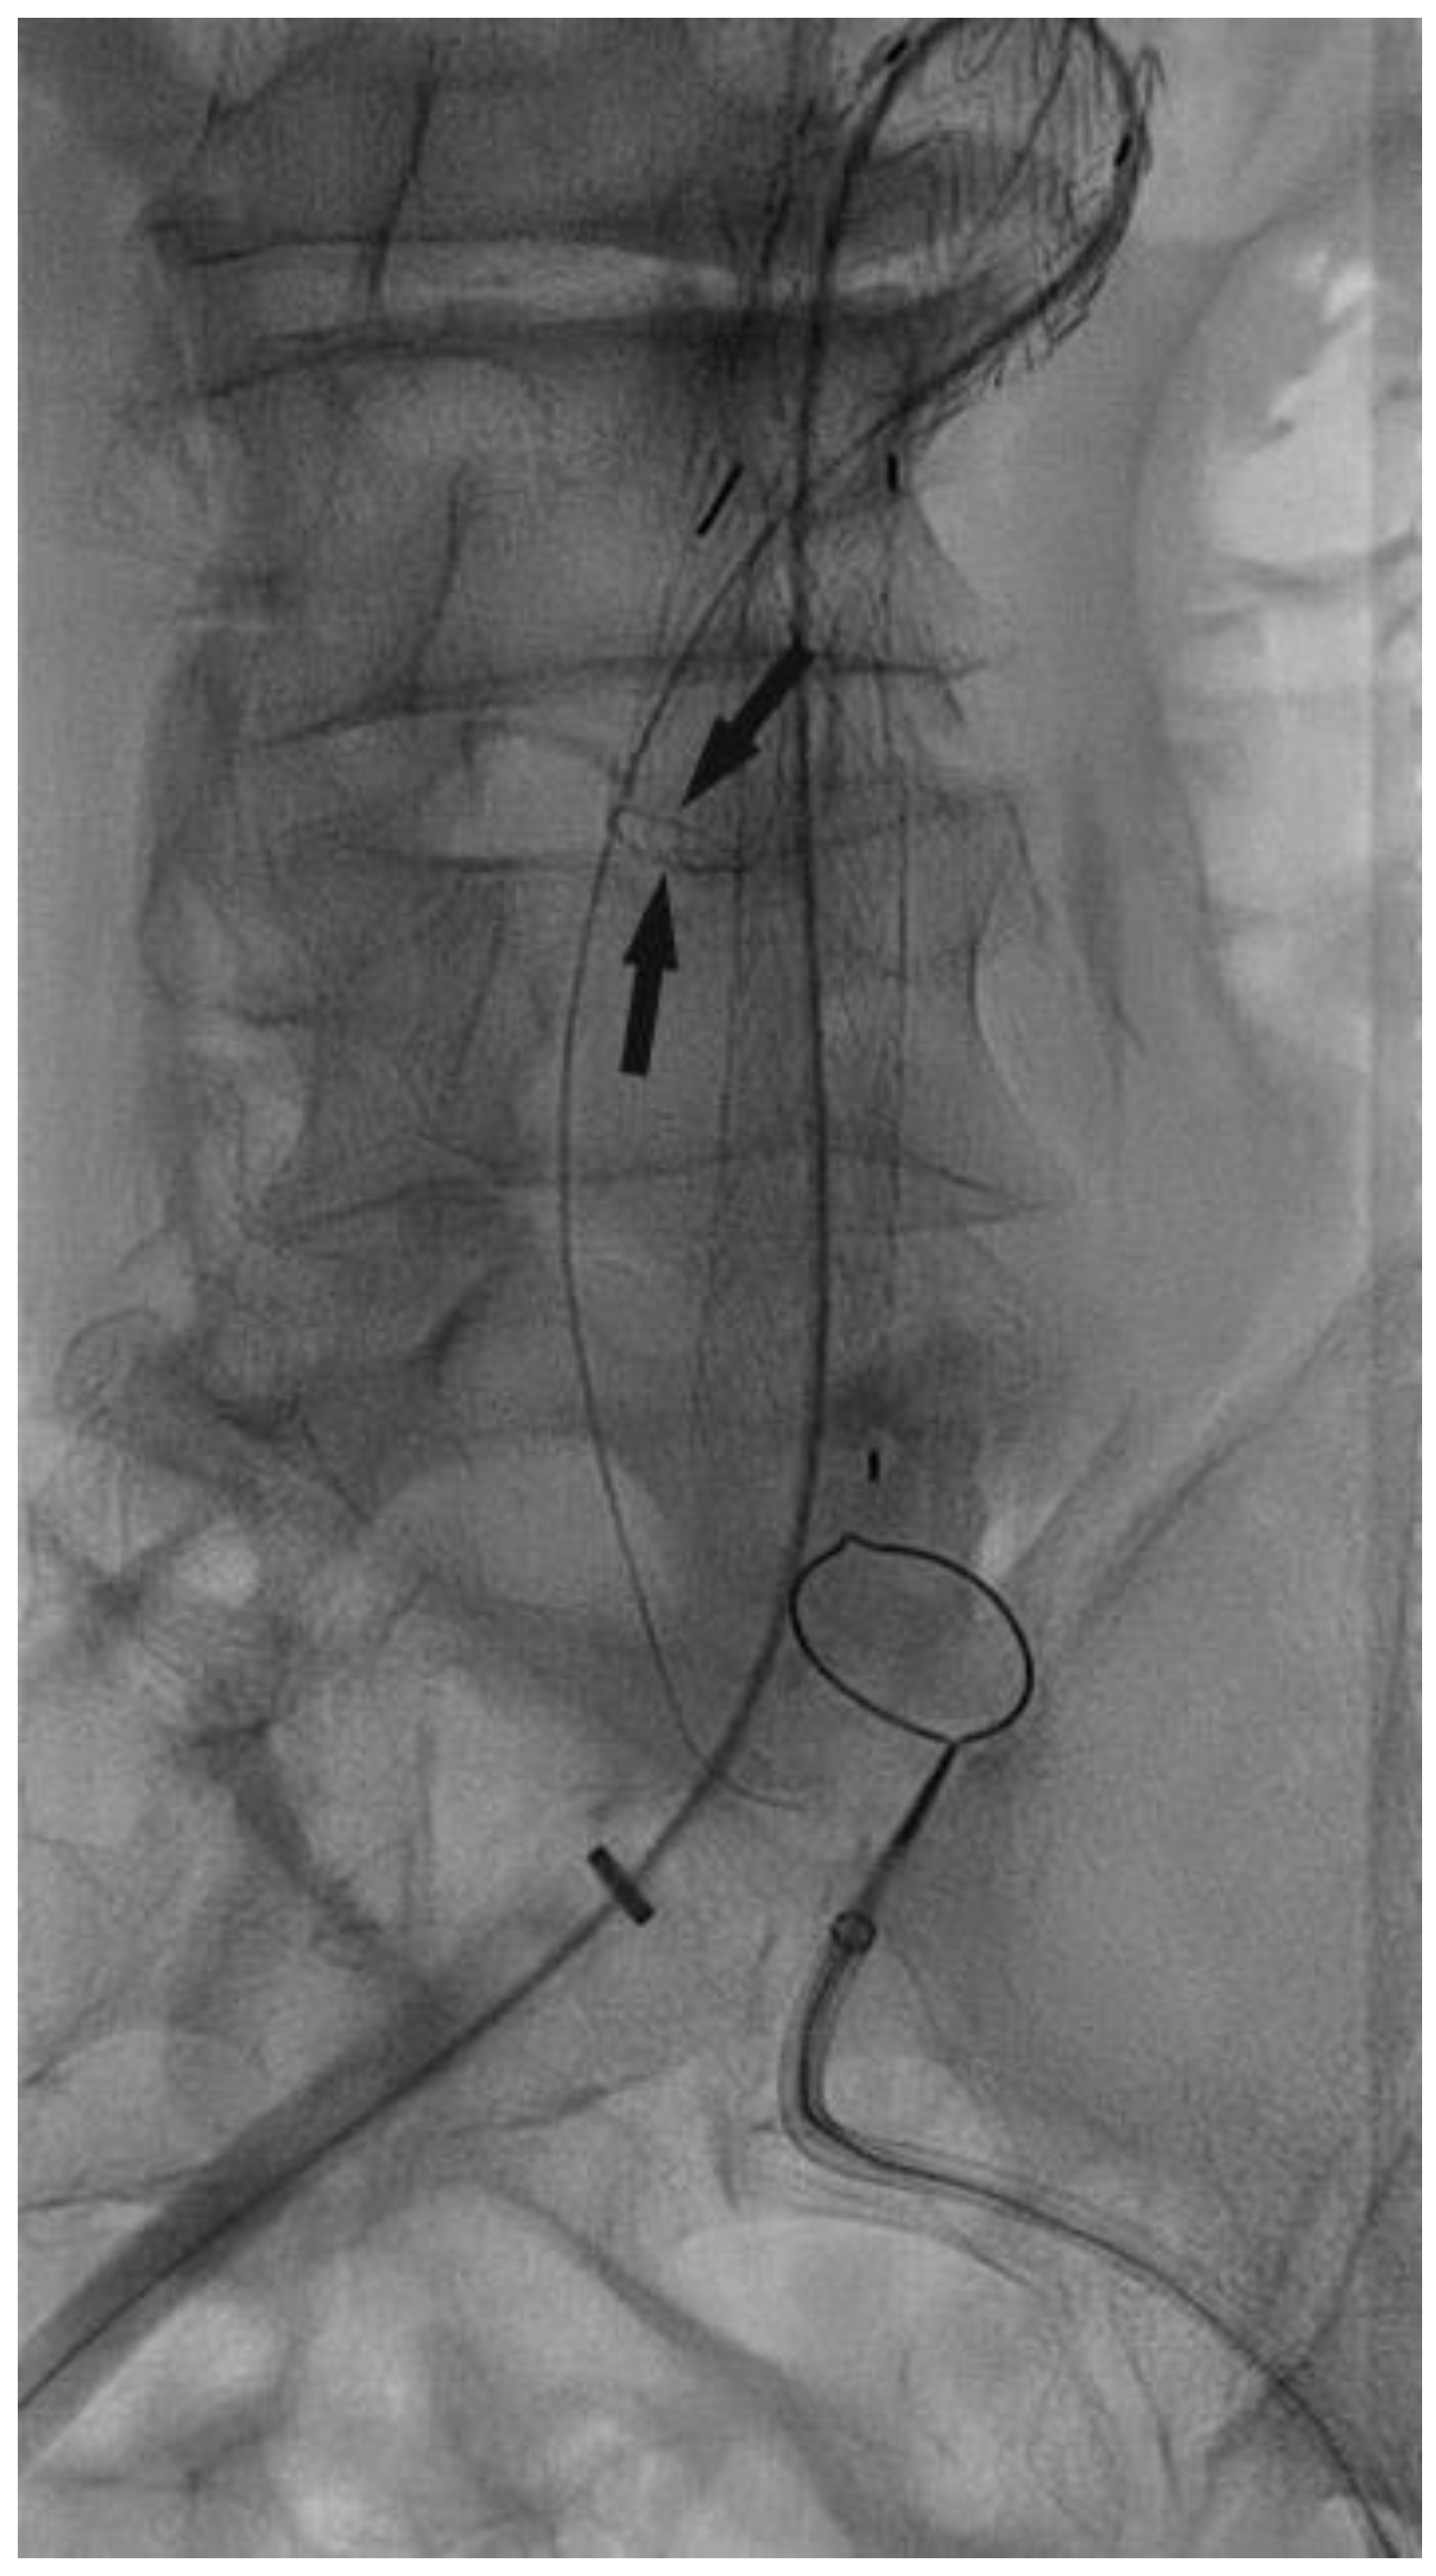

Surgical Technique